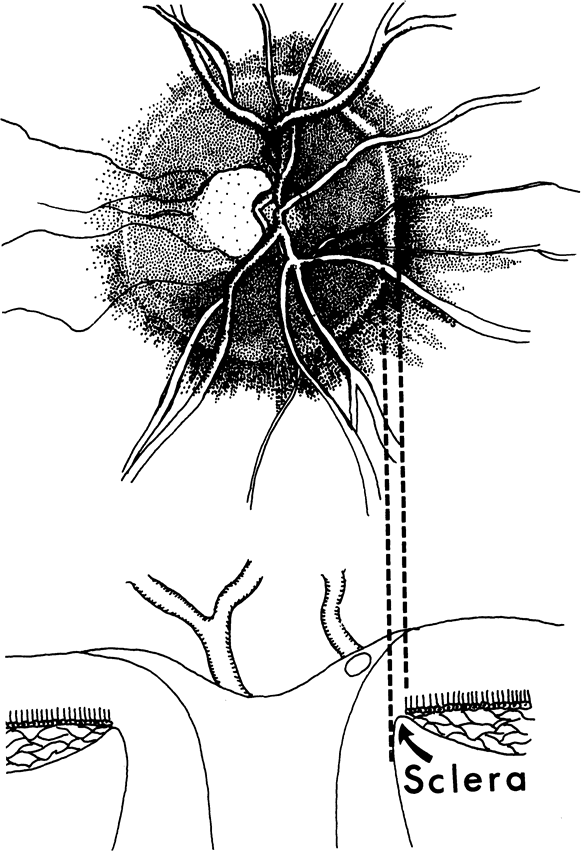

In the retinal nerve fiber layer, axons converge from every direction toward the optic disc and turn to enter the optic nerve through an opening in the outer retina, the choroid, and the sclera. The features and anatomic variation of the normal optic nerve head, or optic disc, are illustrated in Figures 2, 3, 4, 5, 6, 7, 8, 9, 10, 11, 12, 13, 14, 15, and 16. A physiologic excavation (cup) results if the chorioscleral canal is larger than required for the approximately 1 to 1.5 million axons and the supporting glial cells and blood vessels. The size of the excavation depends on how ample is the size of the chorioscleral canal.20,21 In discs where the chorioscleral canal matches the number of axons, the chorioscleral canal itself is typically somewhat taller than it is wide (Figs. 2 and 3). However, because the number of nerve fibers entering the upper and lower poles of the disc is greater than in the temporal and nasal sectors, the boundary of the physiologic cup is more or less circular.22 When the disc is large, it may be nearly circular but the cup likewise nearly circular. However, except in discs of anomalous shape, the width of the rim of neuroretinal tissue is noted in normal, nonglaucomatous optic discs to be greatest in the inferior meridian followed by the superior meridian, and narrowest in the temporal quadrant.23

Fig. 2. Normal optic nerve configuration. Notice that the height (H) of the disc is greater than the width (W). The width of the neuroretinal tissue (A) is also greater in the vertical meridian than in the nasal and temporal meridians (B); thus, the physiologic cup is round.

Fig. 3. Normal disc untilted, taller than it is wide. The neuroretinal tissue in the upper and lower sectors is more abundant in these sectors than others, so the central cup is round. A narrow white line marks the disc boundary and represents the lip of sclera that in humans almost universally separates the choroid from the optic disc tissue around the entire circumference.